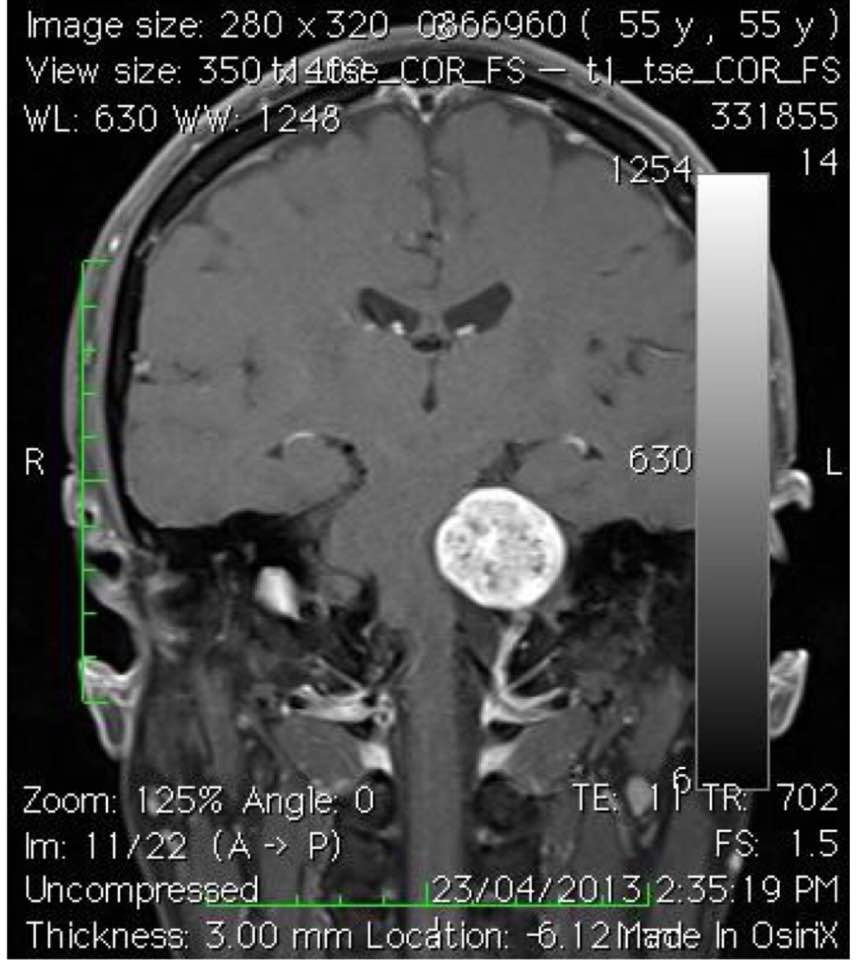

2017-05-16 By Medical Excel Medical Group2017-5-16 保護聽覺和面部神經的微創顯微鏡腦神經外科手術, 結合手術三個月後的Cyberknife放射治療 4年前的6小時顯微鏡手術下,我要非常謹慎及技巧地保存你的聽覺神經和面部神經線, 借助腦神經線功能手術中的監察系統, 幫你進行腫瘤囊內的切除術. 為着的是要保留您的聽覺神經和面部神經線, 因為兩條神經線都貼附及結合在腫瘤之囊壁. 手術後, 您繼續享有與手術前一樣的良好聽力 術後3個月, 我再利用Cyberknife放射治療來控制餘下的三成腫瘤生長並使其收縮 . 雖然您的聽力稍微受到Cyberknife的輻射效應影響, 但與其他患有同樣大的聽覺神經腫瘤的病者相比, 您已經享有最佳的臨床治療效果. 4年後的今天, 你左耳的聽力仍是一樣的保存良好, 可享受你的退休生活. (#) 此為個別案例,實際成效因人而異。 筆者 彭家雄 腦神經外科專科醫生 香港大學內外全科醫學士英國愛丁堡皇家外科醫學院院士香港外科醫學院院士香港醫學專科學院院士(外科) 更多 Excel Medical Group Share :